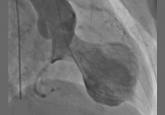

ArticleThis is not an acute coronary syndromeAuthor:Lawrence J. Sinak, MDPublish date: May 1, 2016Stress cardiomyopathy—broken heart syndrome—typically affects older women exposed to a stressful life event.Read More